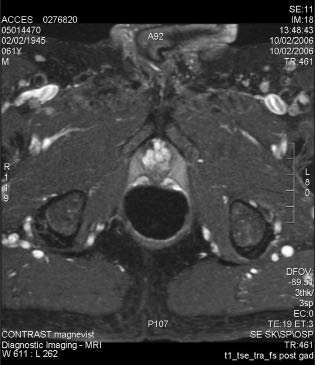

9) Retained “slough” that is preventing adequate bladder emptying can usually be resected or scraped out with a cold loop. The ultimate goal is that, after the sloughing of the ablated tissue, there will be a significant prostate defect as shown in the MRI images before and after HIFU treatment, Figure 5.